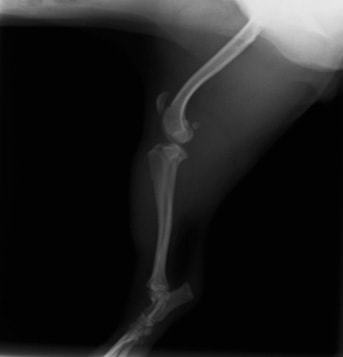

■ 症例20 ポメラニアン 8ヶ月 1.8kg

左右膝蓋骨脱臼 グレードⅢ

2ヶ月前から間欠的跛行が認められ、両膝の膝蓋骨脱臼整復術を行った。

手技は縫工筋及び内側広筋の解放、脛骨粗面の外側転位、滑車ブロック形造溝術、内外側関節包の縫縮を選択し実施した。

右側の膝蓋骨脱臼は上記手技で整復されたものの、左側はそれのみでは膝蓋骨が浮く様子が認められた。その為、PDS縫合糸にて膝蓋靱帯を1糸のみ縫合し、靱帯の縫縮を行った。

膝蓋骨脱臼は膝関節における膝蓋骨の内外側の脱臼と定義されるが、時として単純な内外の脱臼ではなく、膝蓋骨が大きく前方に浮き上がるように脱臼する場合がある。特にトイプードルやポメラニアンといった犬種に多く認められる。

内側脱臼に加えて前方への浮き上がりを矯正する為に、従来より脛骨粗面転移により膝蓋靭帯を外方と下方に引っ張り、固定する方法を選択する。膝蓋骨の前方への浮き上がりが軽度の場合は、従来法ではなく関節包の縫縮で対応していた。しかし、一部の症例で膝蓋骨の動きが悪くなり伸展機構が円滑に機能せずロボット様歩行になるケースがあった。

その為、膝蓋靭帯自体を縫縮する方法を採用した。この方法により、膝関節の伸展機構を妨げず膝蓋骨の軽度の浮きを矯正することが可能となった。

本症例の経過は良好である